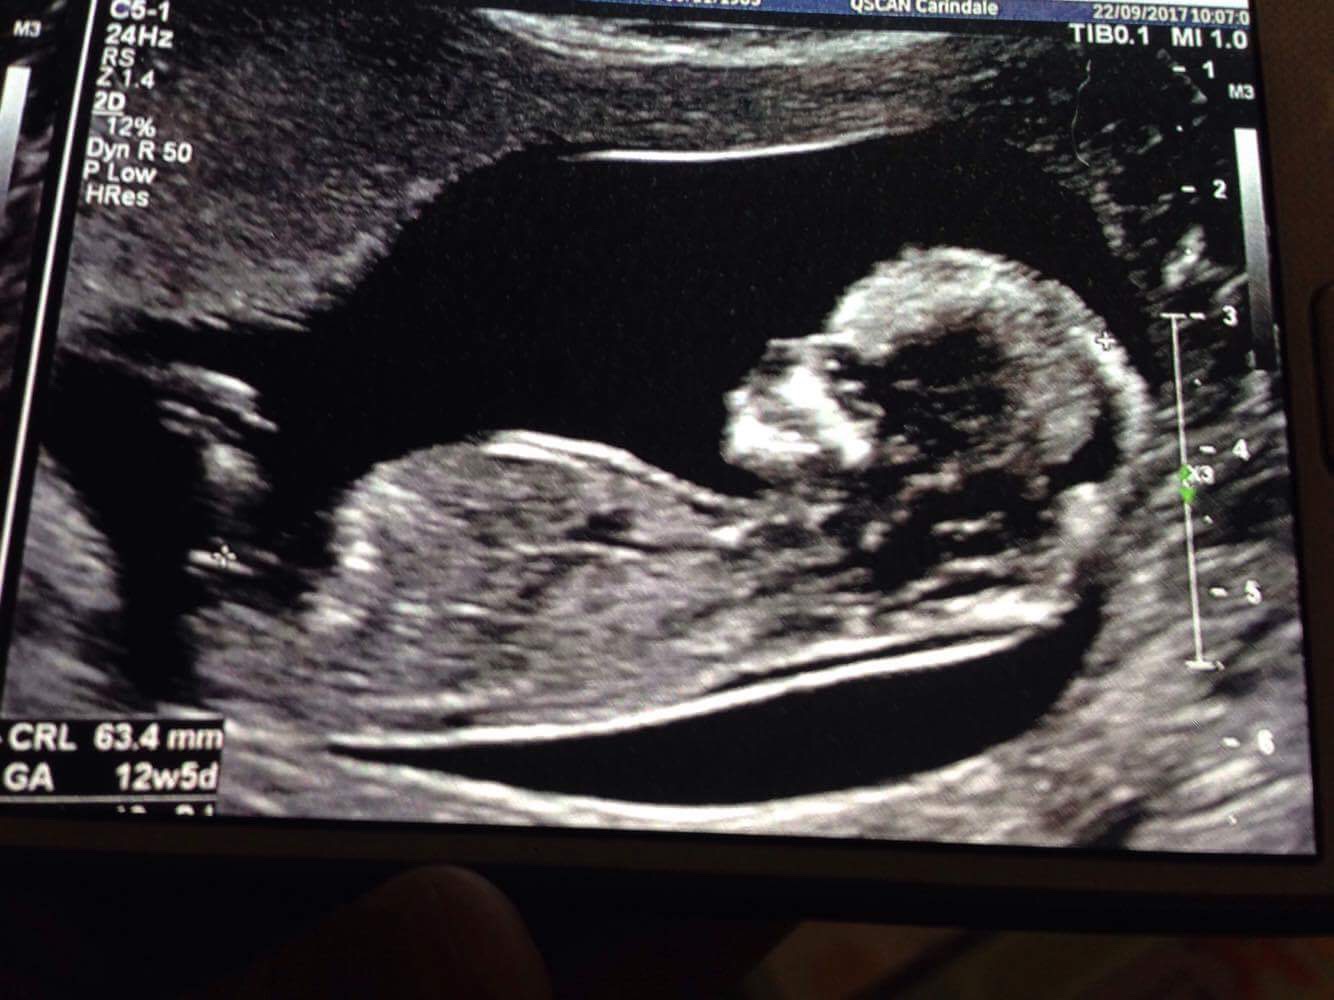

Boy

Sent from my SM-G930F using Tapatalk

Do you have any more photos? I'm leaning girl.

I think boy

Leaning Pink